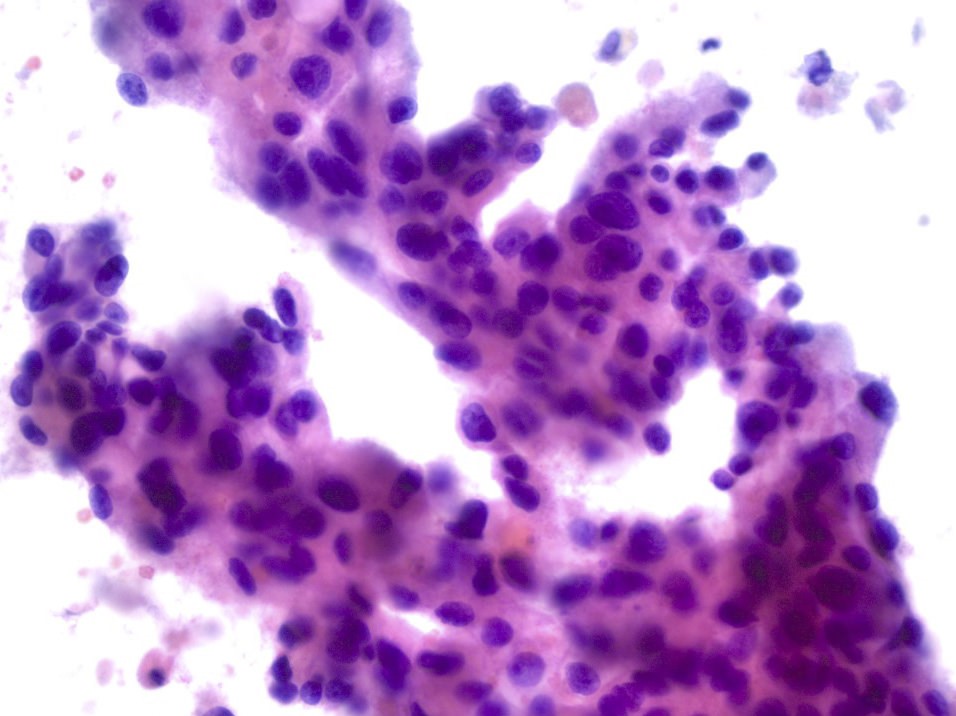

Salivary Duct Carcinoma Cytology Salivary Duct Carcinoma Cytology: Diagnostiek En Kenmerken

Salivary duct carcinoma cytology toont belangrijke kenmerken voor de diagnose van deze agressieve speekselklierkanker.